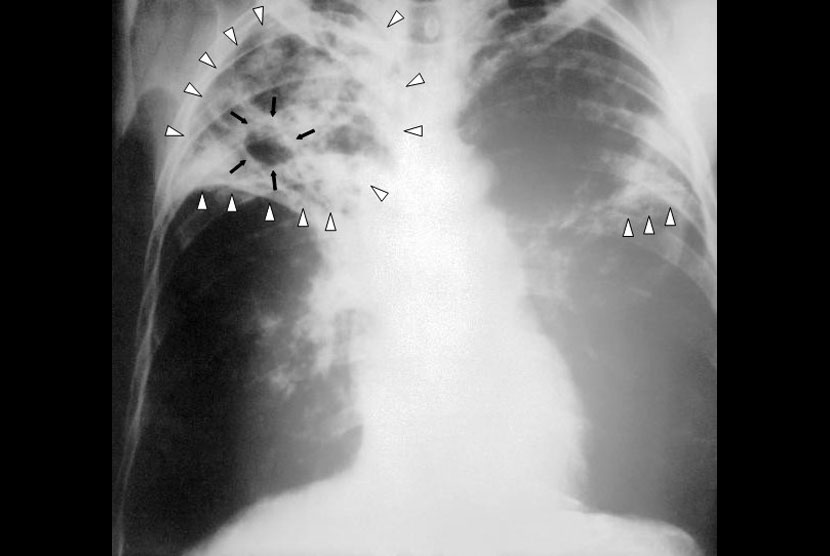

Pekanbaru Sumbang Kasus Terbanyak TBC

RIAUMANDIRI.CO- Berdasarkan data yang dimiliki Dinas Kesehatan Riau, selama tahun 2022 total temuan kasus TBC di Riau mencapai 13.007 kasus, jumlah tersebut tersebar di 12 kabupaten/kota di Riau. Pekanbaru catatkan jumlah penderita terbanyak di Riau.

Kepala Dinas Kesehatan Riau Zainal Arifin mengatakan, di Pekanbaru kasus TBC tercatat mencapai 3.887 kasus, Kampar 1.230 kasus, Rokan Hilir 1.220 kasus, Rokan Hulu 1.133 kasus, Bengkalis 1.105 kasus. Indragiri Hilir 933 kasus.

"Kemudian Dumai 901 kasus, Pelalawan 782 kasus, Siak 590 kasus, Indragiri Hulu 557 kasus, Kuantan Singingi 444 kasus dan Kepulauan Meranti 225 kasus," paparnya.

Sementara itu, untuk penanganan TBC di Riau, dapat melakukan diagnosis sesuai standart (melalui pemeriksaan TCM). Memberikan obat sesuai standart yang ditetapkan. Melakukan Follow up terhadap pasien TBC sesuai standart.